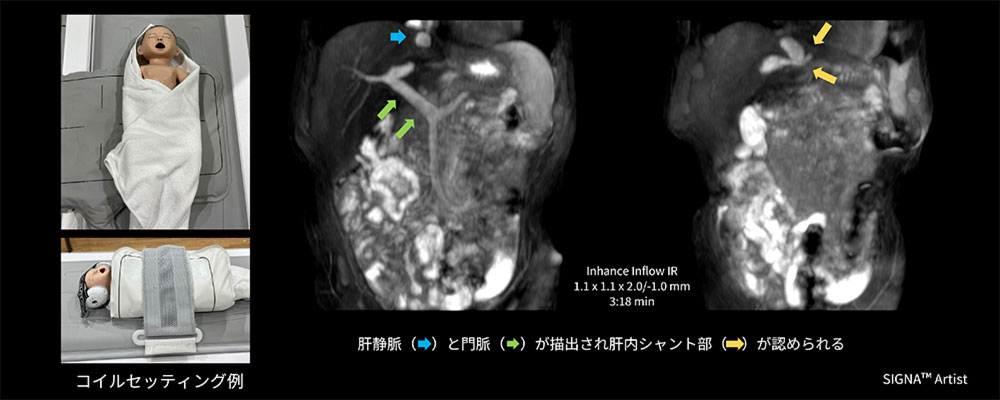

Case4  新生児の門脈肝静脈シャント非造影検査

生後6か月の乳児。超音波検査時にて体循環門脈シャントを指摘されており、複数シャントの有無、血管腫の有無についてMRI検査を実施。ポジショニング時にGEM Flex Coilの使用を検討したが、体動や患児の固定及びコイルの固定が懸念されたため、MP Coil を使用し検査を施行。

AIR™ Coilsに使用シーケンスの制限はないため、Inhance Inflow IRで検査を実施。門脈P3と左肝静脈間にシャント形成を認め、その他シャント形成は認められなかった(図6)。

結果として患児の体型に合わせてコイルをフィットさせることができ、ポジショニングも簡便かつスムーズに行うことができた結果、追加鎮静もなく迅速な検査実施に貢献できた一例。

AirCoils_Shigaikadai_07.jpg図6 新生児の門脈肝静脈シャント非造影検査におけるMP Coilのセッティング例と臨床画像